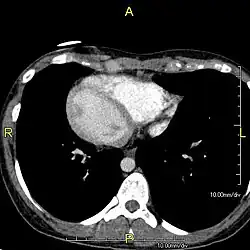

Dextrokardie

Mit dem Begriff Dextrokardie (Rechtsherzigkeit), abgeleitet von altgriechisch δεξιός dexiós, deutsch ‚rechts‘ und altgriechisch καρδία kardía, deutsch ‚Herz‘, wird in der Medizin ein Phänomen bezeichnet, bei dem sich das Herz ständig oder zeitweilig in der überwiegend rechten statt in der linken Brusthöhle befindet.

Eine Dextrokardie kann angeboren im Rahmen eines sogenannten Situs inversus (totalis) auftreten,[1] bei dem im Brustkorb oder auch im ganzen Körper sämtliche Organe spiegelverkehrt angelegt sind. Auch kann Dextrokardie durch eine Herzdrehung entstanden sein, etwa als Folge einer Lungen- oder Brustfellerkrankung.